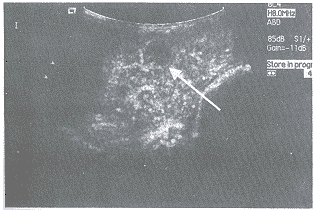

视觉造影效果 二次谐波和基波显像在造影剂量增加时有轻度视觉评分提高。组间肿瘤显影的视觉评分对比在两种显像的0.01与0.04剂量水平之间有统计学差异(P<0.05),在相同剂量水平二次谐波视觉评分明显高于基波显像(见图1、2、3),两种显像方式有非常显著的差别(P<0.01)。

图1 二次谐波显像造影,在0.01剂量水平肿瘤轻度显影(白箭头),肝实质轻度增强。